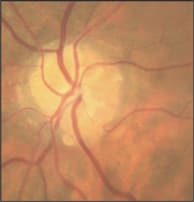

Angioid streaks are irregular, jagged, radiating lines that surround the optic disc and extend outward radially. They lie deeper than the retinal vessels and represent dehiscences in the collagenous and elastic portion of Bruch's membrane. These lines were first described in 1889 by Doyne and have a crackline appearance.1 In 1892, Knapp proposed to call them angioid streaks because they resembled vessels. They can vary in color depending on the pigmentary characteristics of the underlying choroid, from reddish orange to dark red or brown (Figures 1 and 2).

Figure 1. This color picture reveals the irregular, dark colored, radiating lines that surround the optic disc (left).

Figure 2. The streaks appear as dark gray irregular lines in this red-free photo (right).